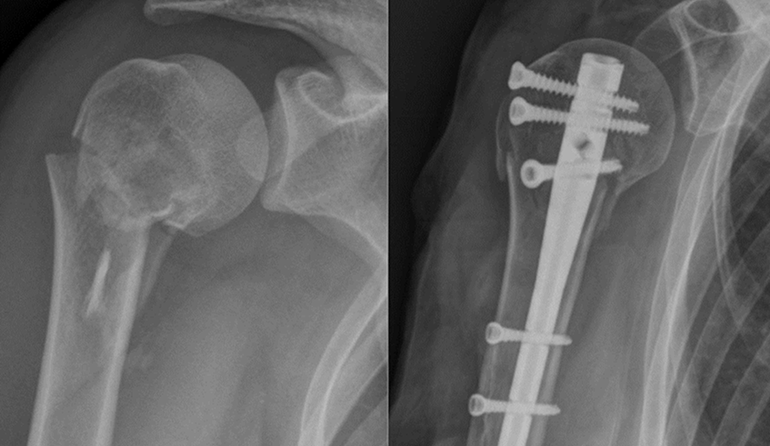

El húmero es el hueso más largo del brazo, ubicado entre el hombro y el codo. Las fracturas más comunes afectan la zona proximal (cabeza del húmero), aunque también pueden darse en el cuerpo del hueso (diáfisis) o en la zona distal (cerca del codo). Estas lesiones suelen ocurrir por golpes fuertes o caídas.